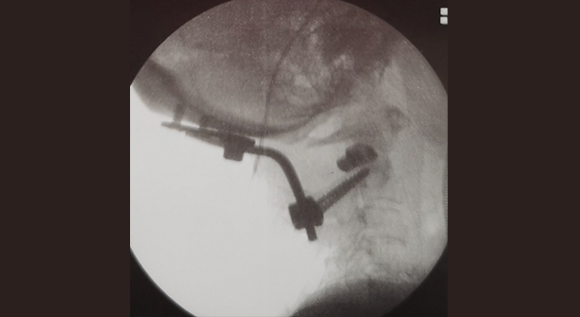

脊柱脊髓神经微创中心以微创技术为引领,以功能恢复为目标,主要治疗脊柱外伤、肿瘤、退行性病变、脊柱畸形等疾病。团队利用神经外科显微技术,结合神经内镜微创技术,对脊柱间盘变性疾病、颈腰椎管狭窄、颈腰椎间孔狭窄、颈腰椎间盘突出、颈腰椎体不稳、脊柱骨折、寰枢椎脱位、脊柱肿瘤、椎管内肿瘤、脊髓损伤、脊髓空洞、脊髓栓系等疾病进行高效、特色手术治疗,如颅颈交界区畸形寰枕减压内固定术、脊柱肿瘤全脊椎切除内固定术、微创椎管内肿瘤切除术、微创脊柱旁肿瘤切除术、寰枢椎脱位椎间融合内固定术、脊柱骨折微创经皮椎弓根钉内固定术、经椎间孔椎间融合内固定术(MIS—TLIF)等,最大程度降低脊柱脊髓手术创伤,具有创伤小、输血少、恢复快、口碑好,出院早等优势。